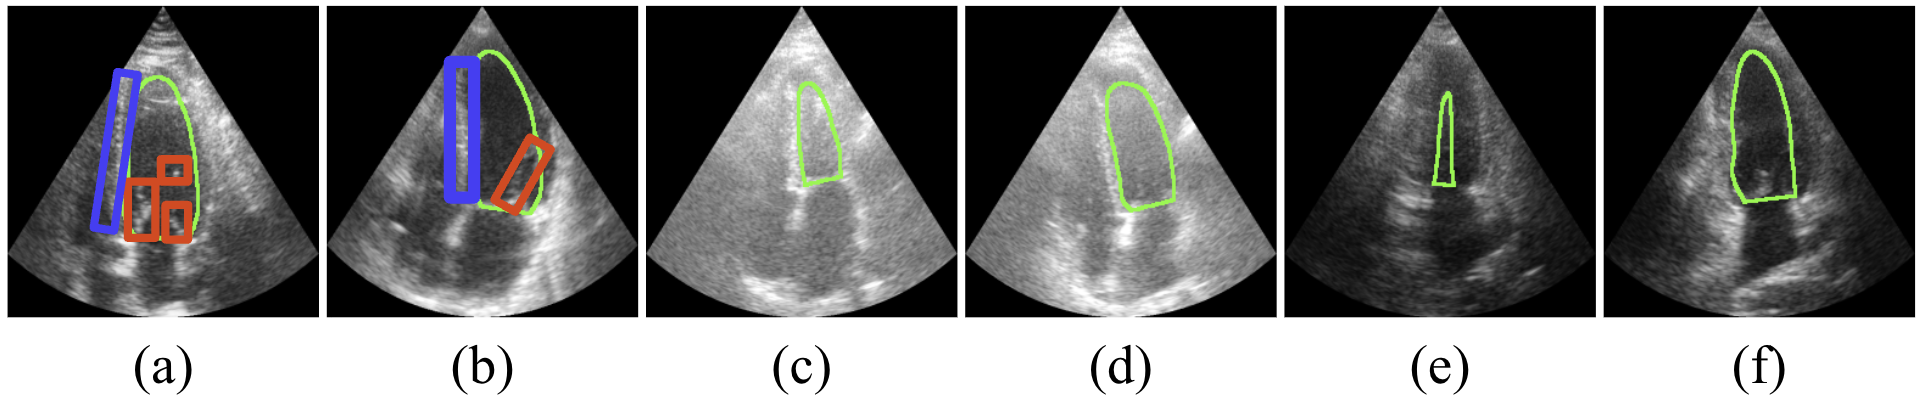

Medical

(a)Speckle Noise, (b)Blurred Contours, and (c-f)Pronounced Variations in the Target's Morphology Across the Cardiac Cycle